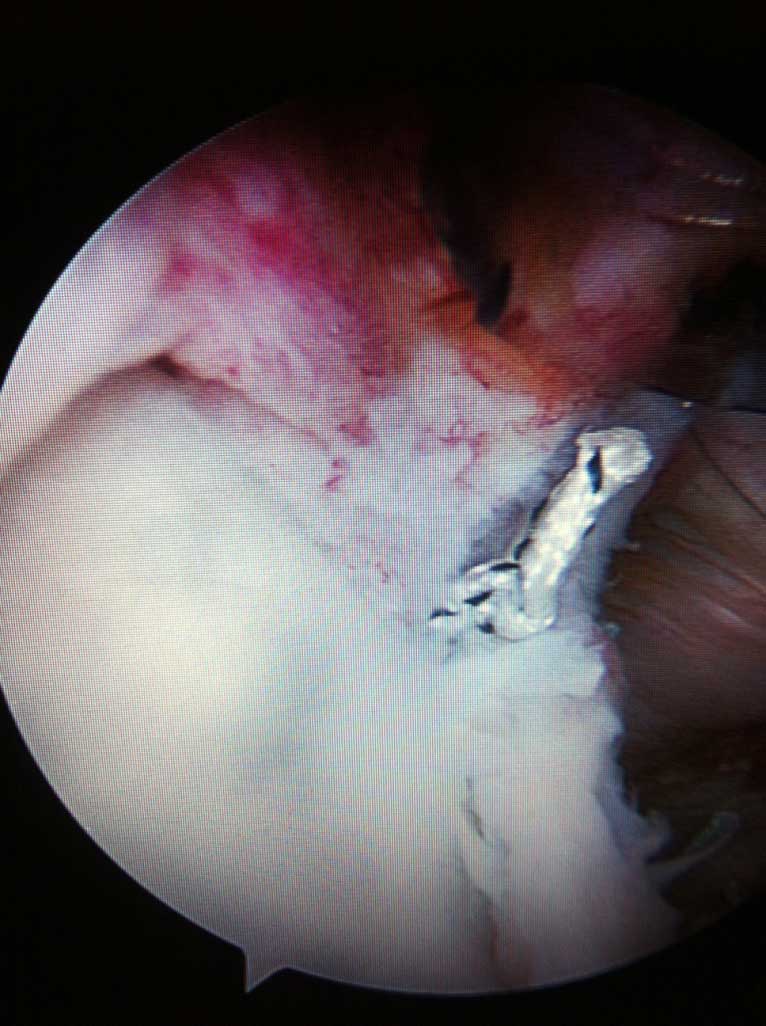

Je nach Alter, Verletzungsmuster, Anzahl der Luxationsereingnisse und weiteren Faktoren, wird eine schulterstabilisierende Operation indiziert und empfohlen. Diese führen wir ebenfalls ausschliesslich arthroskopisch

(Schüsselloch Operation) durch. Innerhalb von 15 - 30 min wird dabei der knorpelige Ring (s.g. Labrum) auf den knöchernen Pfannenrand mit speziellen Anker und Fäden wieder zurück befestigt.

Wie auf der Bilddokumentation ersichtlich, wird die Kontaktfläche zwischen der kleinen knöchernen Pfanne und dem Kopf durch einen knorpeligen Ring, s.g. Labrum, der sich am Pfannenrand befindet, vergrössert.